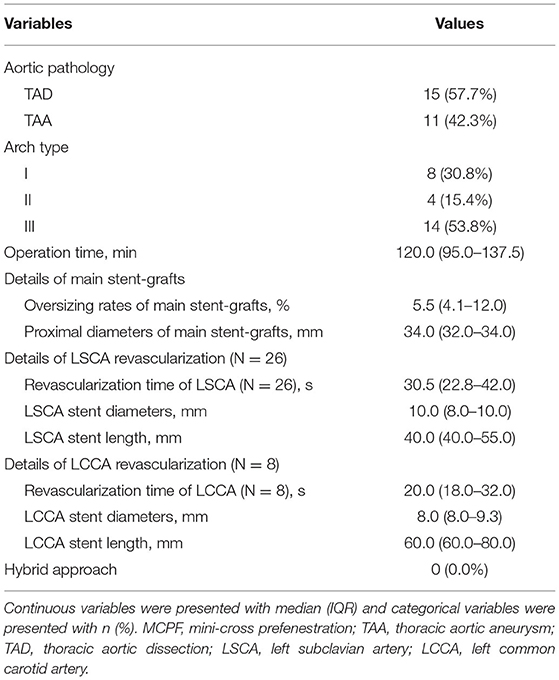

From December 2017 to February 2020, a total of 26 cases (22 males, median age 63 years) were performed with the MCPF technique in our center. Among them, there were 22 (84.6%) cases with hypertension, 1 (3.8%) case with diabetes mellitus (DM), 2 (7.7%) cases with preoperative cerebral infarction, 2 (7.7%) cases with coronary artery diseases (CAD), 1 (3.8%) case with cardiac insufficiency, 1 (3.8%) case with chronic kidney disease (CKD), and 6 (23.1%) cases with chronic obstructive pulmonary disease (COPD) (Table 1).

Details of Endovascular Procedure

Table 2 demonstrates the details of the endovascular procedure. There were 15 (57.7%) cases of TAD and 11 (42.3%) cases of TAA. There were 8 (30.8%) type I aortic arches, 4 (15.4%) type II aortic arches, and 14 (53.8%) type III aortic arches. The median operation time of the MCPF group was 120.0 (IQR, 95.0–137.5) min. Eighteen (69.2%) patients underwent the reconstruction of the LSCA only. The fenestrations of both the LSCA and LCCA were conducted in 8 (30.8%) patients. The median revascularization time of the LSCA and LCCA was 30.5 (IQR, 22.8–42.0) s and 20.0 (IQR, 18.0–32.0) s separately. The median diameters of the main stent grafts were 34.0 (32.0–34.0) mm and the median oversize rate was 5.5% (IQR, 4.1–12.0%). The median diameters of the LSCA and LCCA branch stents were 10.0 (IQR, 8.0–10.0) mm and 8.0 (IQR, 8.0–9.3) mm. The median lengths of the LSCA and LCCA branch stents were 40.0 (IQR, 40.0–55.0) mm and 60.0 (IQR, 60.0–80.0) mm. No hybrid approach was operated in any case.

Primary Outcomes

Table 3 demonstrates the primary outcomes of patients receiving the MCPF technique. The postimplantation DSA suggested that no type I/III endoleak or migration was found immediately after the procedure. Furthermore, there were no postoperative MACCE 30 days after TEVAR. The median length of stay was 10.5 (IQR, 8.0–12.5) days.